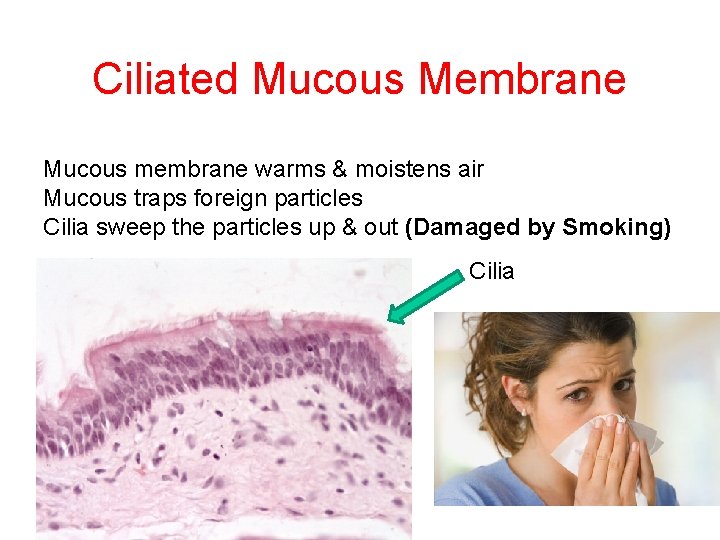

Ciliated Mucous Membrane Mucous membrane warms & moistens air Mucous traps foreign particles Cilia sweep the particles up & out (Damaged by Smoking) Cilia